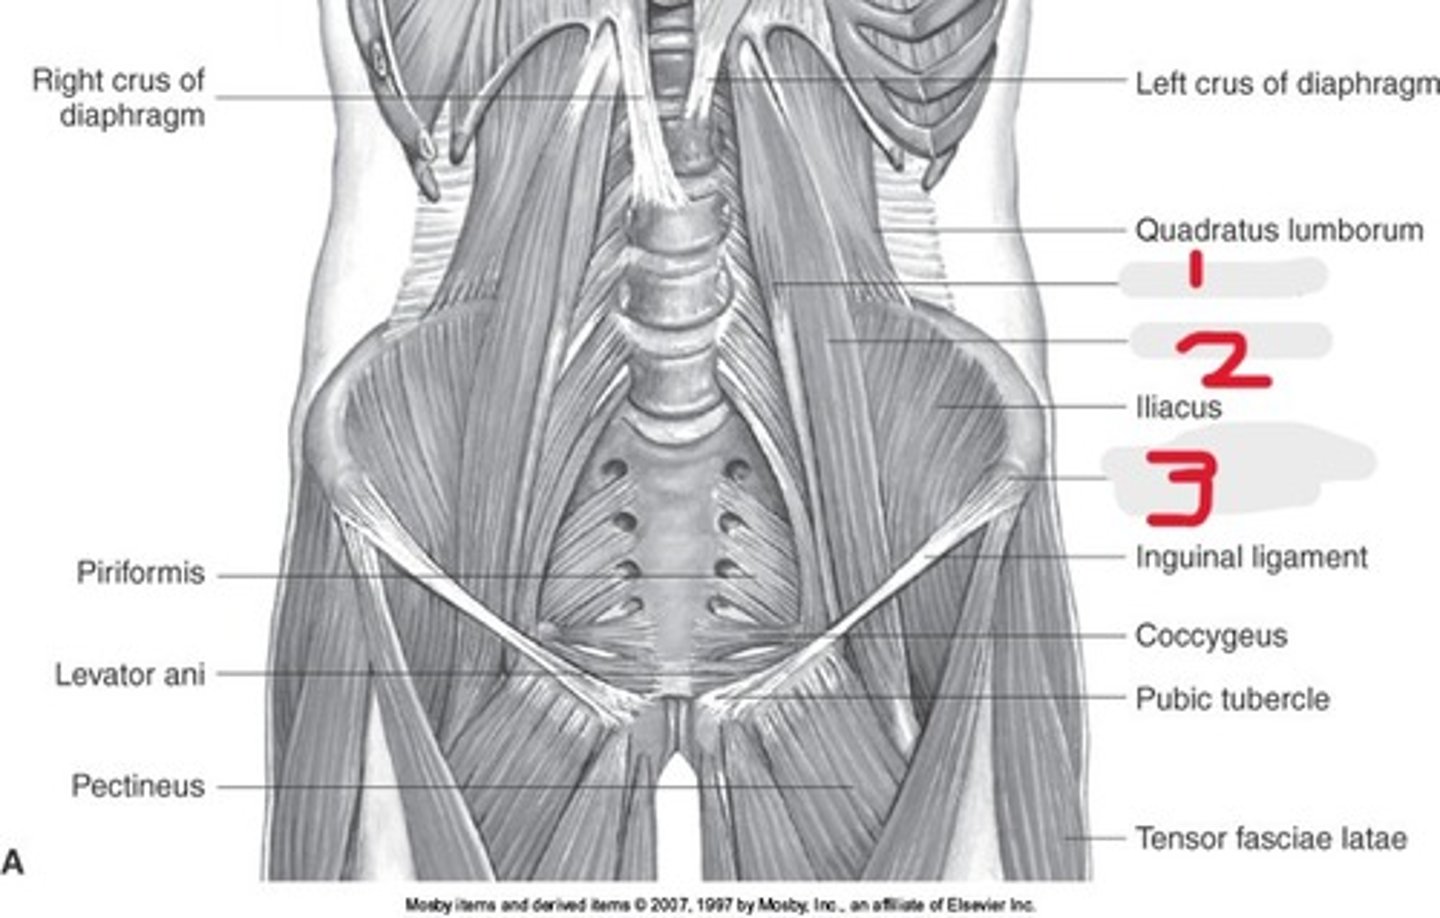

1) Psoas minor

2) Psoas major

3) ASIS

Name all numbered structures

1) Psoas muscle

2) Cauda equina

Name all numbered structures